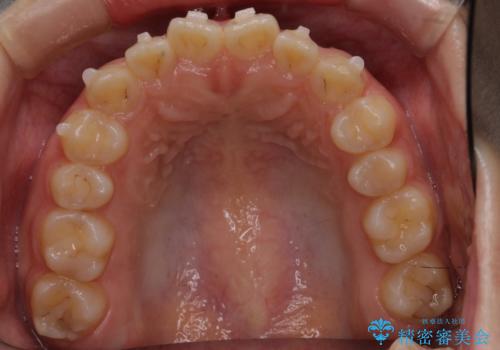

前歯のねじれ 乳歯を残して矯正治療

- 前歯のねじれを気にして来院。

左下に乳歯が残っていましたが、被せ物に穴が空いている状態でした。

乳歯は抜かずに保存的な治療を行いました。

上下の正中が1本分ずれていましたが、ちょうど1本分で目立たず、また、右下の歯が生まれつき少ないことを利用して、最小限の歯の移動にとどめました。